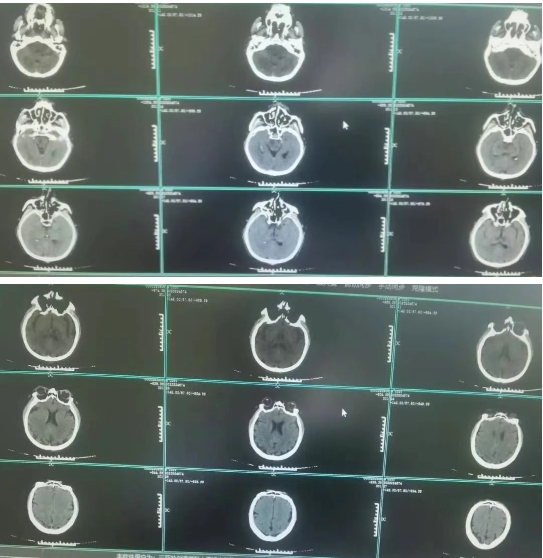

56岁的沙先生,是一名远洋渔船作业人员,工友发现意识不清10余小时。既往甲亢,房颤病史。入院查体深昏迷,刺痛无反应,四肢无活动,双侧病理征阳性,头颅CT提示未见脑内出血。入院诊断:急性基底动脉闭塞,脑干梗塞,房颤。实施术式:脑血管造影,基底动脉机械取栓,脑动脉导管溶栓手术�术中造影可见基底动脉闭塞,考虑血栓脱落导致。不及时开通,致死的可能性大�进一步采取支架及取栓导管抽吸取栓,微导管动脉内溶栓手术方式,及时开通了基底动脉主干及主要分支�患者术后刺痛反应较前改善,浅昏迷。经气管切开,脱水,改善脑循环等积极治疗后,病情稳定后转回当地樱花动�